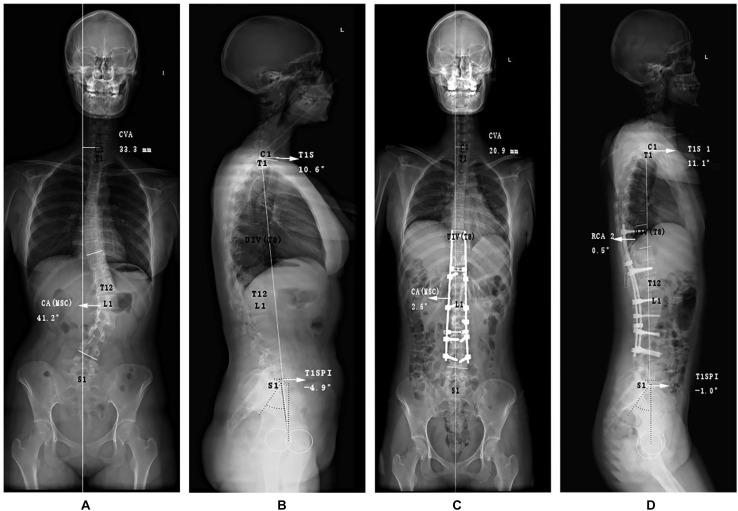

Statistical differences between PJK and non-PJK groups were as follows: gender ( = 0.001), preoperative factors [thoracic kyphosis ( = 0.03), T1 slope angle (T1S, = 0.078)], and postoperative factors [T1S ( = 0.097), proximal junctional angle ( = 0.003), upper instrumented vertebra (UIV) - UIV + 1 ( = 0.001)]. Random forest using SMOTE achieved the best prediction performance with AUC = 0.944, accuracy = 0.909, and F1 score = 0.667 on independent testing dataset. Cox model revealed that male gender and larger preoperative T1S were independent prognostic factors of PJK (odds ratio = 10.701 and 57.074, respectively). Gender was also at the first place in the importance ranking of the model with best performance.

PJK组和非PJK组之间的统计学差异如下:性别(P = 0.001)、术前因素[胸椎后凸(P = 0.03)、T1斜率角(T1S,P = 0.078)]和术后因素[T1S(P = 0.097)、近端交界角(P = 0.003)、上固定椎(UIV)-UIV + 1(P = 0.001)]。在独立测试数据集上,使用SMOTE的随机森林模型具有最佳预测性能,AUC = 0.944,准确率 = 0.909,F1评分 = 0.667。Cox模型显示男性性别和术前较大的T1S是PJK的独立预后因素(比值比分别为10.701和57.074)。在性能最佳的模型的重要性排名中,性别也位居首位。